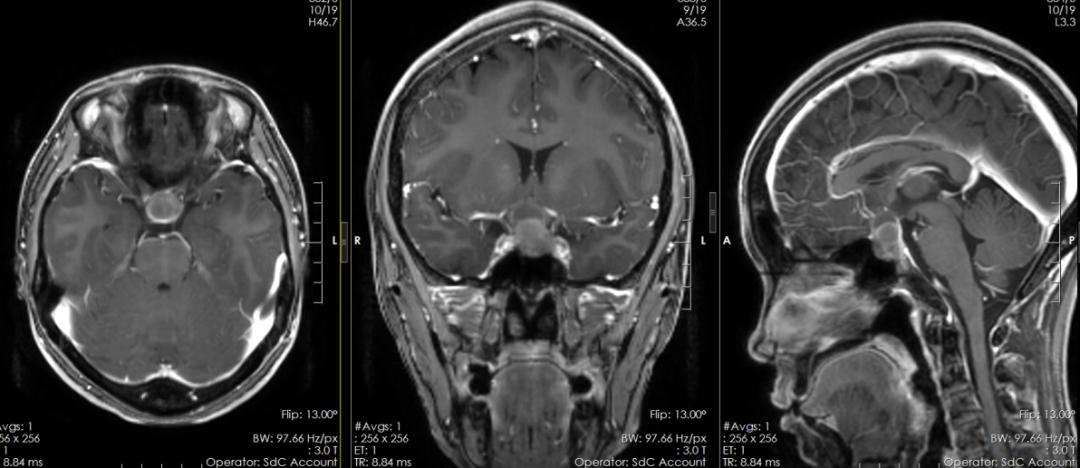

▲术前磁共振

我院神经外九科主任穆林森接诊了患者。穆林森仔细查看了患者过往的影像检查资料后,分析患者鞍内及鞍上示一范围约21mm×15mm×18mm的团块状不均匀稍高低混杂信号影,考虑垂体腺瘤可能性大。

穆林森分析,由于肿瘤部分包绕颈内动脉,视交叉及垂体柄受压,鞍底下陷、鞍隔膨隆,这才引起患者出现明显的视力下降。此外,患者性激素检查结果提示泌乳素明显升高,患者出现“停经”的问题极可能与垂体瘤有关。